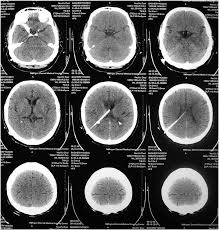

Brain Ct Scans Showing Normal Ventricles After Ventriculoperitoneal Download Scientific Diagram